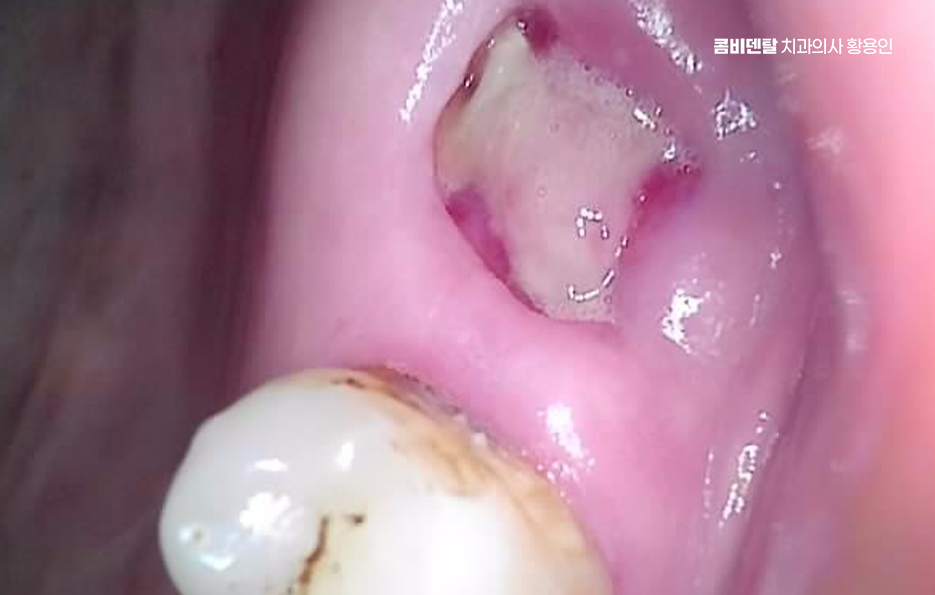

출처 아카이브 열기처음 어금니를 하나 잃었을 땐 그렇게까지 큰일은 아니라고 생각했어요. 충치가 너무 심해서 결국 발치를 하게 됐고, 치과 선생님은 빠진 자리를 임플란트로 채우는 게 좋겠다고 권하셨지만, 솔직히 당시엔 시간도, 돈도 여유가 없었고, 또 막상 하나쯤 없다고 해서 일상이 크게 불편하진 않았기 때문에 그냥 좀 불편하더라도 참자고 마음을 먹었어요. 한쪽으로만 씹는 습관이 생겼지만, 그건 생각보다 쉽게 적응됐고, 어금니 하나 없이도 밥을 먹는 데 큰 무리는 없다는 착각 속에서 점점 그 빈자리에 무뎌져 갔어요. 그렇게 몇 달, 몇 년이 흘렀고, 지금 와서 돌이켜보면 그때 치료를 미뤘던 결정이 얼마나 후회로 돌아오는지 스스로도 놀라울 정도예요. 처음 눈에 띈 변화는 반대쪽 어금니에 가해지는 압력이 점점 커졌다는 거였어요. 무의식적으로 계속 반대쪽만 사용하다 보니 그쪽 치아에 피로가 쌓이기 시작했고, 어느 날부터는 씹을 때 약간의 통증과 불편함이 느껴지기 시작했어요. 그때도 아직은 버틸 수 있다고 생각했어요. 통증이 있긴 해도 일시적일 거라 여겼고, 양치만 잘하면 괜찮아질 거라고 안일하게 넘겼어요. 그런데 문제는 그게 단순한 통증이 아니라 구조적인 불균형에서 시작된 거였다는 걸 늦게 깨달았어요. 빠진 어금니의 빈자리를 그대로 두면서 위쪽의 맞물리던 치아가 점점 내려오기 시작했고, 아래쪽 잇몸에 자극을 주기 시작하면서 잇몸이 자주 붓고 시큰거리는 현상이 생겼어요. 그뿐만 아니라 양옆에 있던 치아들이 빈 공간 쪽으로 기울기 시작하면서 음식물이 자주 끼고, 양치해도 개운하지 않은 날이 많아졌고, 결국 또다시 충치가 생기기 시작했어요. 하나의 치아를 잃은 게 끝이 아니라 주변 치아들까지 도미노처럼 영향을 받기 시작했다는 걸 그제서야 알게 된 거죠. 더 무서운 건 턱관절의 문제였어요.

이처럼 치아 상실 후에 임플란트에 대한 중요성을 느끼게 되는 것은 특히 앞니라면 인상을 좌우하는 위치이기 때문에 미루는 경우가 거의 없지만 어금니의 경우 반대편으로 씹으면 되지 않을까 하면서 치료를 미루는 경우가 많지만 어금니 없으면 얼굴 발음 및 편측 저작으로 인한 반대편 치아의 문제, 잇몸 뼈의 흡수 등 여러 문제로 이어질 수 있는데요

더 심각한 건 치열 전체가 무너지는 것으로 어금니가 빠지고 그 자리를 비워 두면, 위에 맞물리는 치아가 점점 내려오거나, 옆 치아가 쓰러져 들어가며 이렇게 정출된 치아는 다시 제자리로 돌아오지 않기 때문에, 나중에 임플란트를 하려고 해도 공간이 맞지 않아서 교정치료를 먼저 해야 할 수도 있었어요.